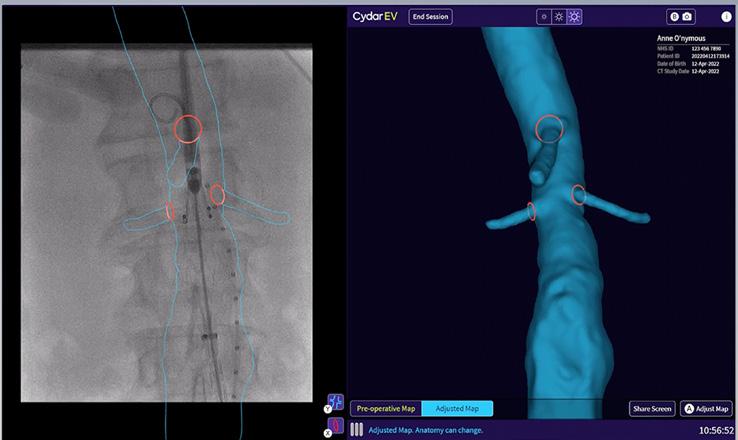

Finally, the presenter gave an overview of the pros and cons of image fusion. He stated that there is one system in this space—the Cydar Medical system—that offers automated registration. This technology compares the anatomy visible on live fluoroscopy with anatomy of a preoperative computed tomography angiography

(CTA) and automatically produces 3D overlay, he explained. According to the presenter, this technology offers “a significant reduction of contrast agent and also reduction of procedure time,” despite having a somewhat “complex setup”. Image fusion is “widely available” and, in the presenter’s opinion, “should be used in all complex procedures”.

Image fusion should be considered during aortic endovascular procedures to reduce radiation exposure.1

During pre-operative planning, Cydar EV Maps processes the CT scan (even if poor quality) to accurately segment the anatomy. This, along with our detailed planning and measurement tools, provides you with the right insights and information at the right time.

Cydar EV Maps automatically adjusts the 3D overlay when changes occur due to C-arm position, patient movement or posture change, minimizing the need for additional registrations.

With Cydar EV Maps, you are able to visualize and navigate vessels, minimizing the need for steep lateral angulation and reducing radiation exposure to clinical teams and patients.